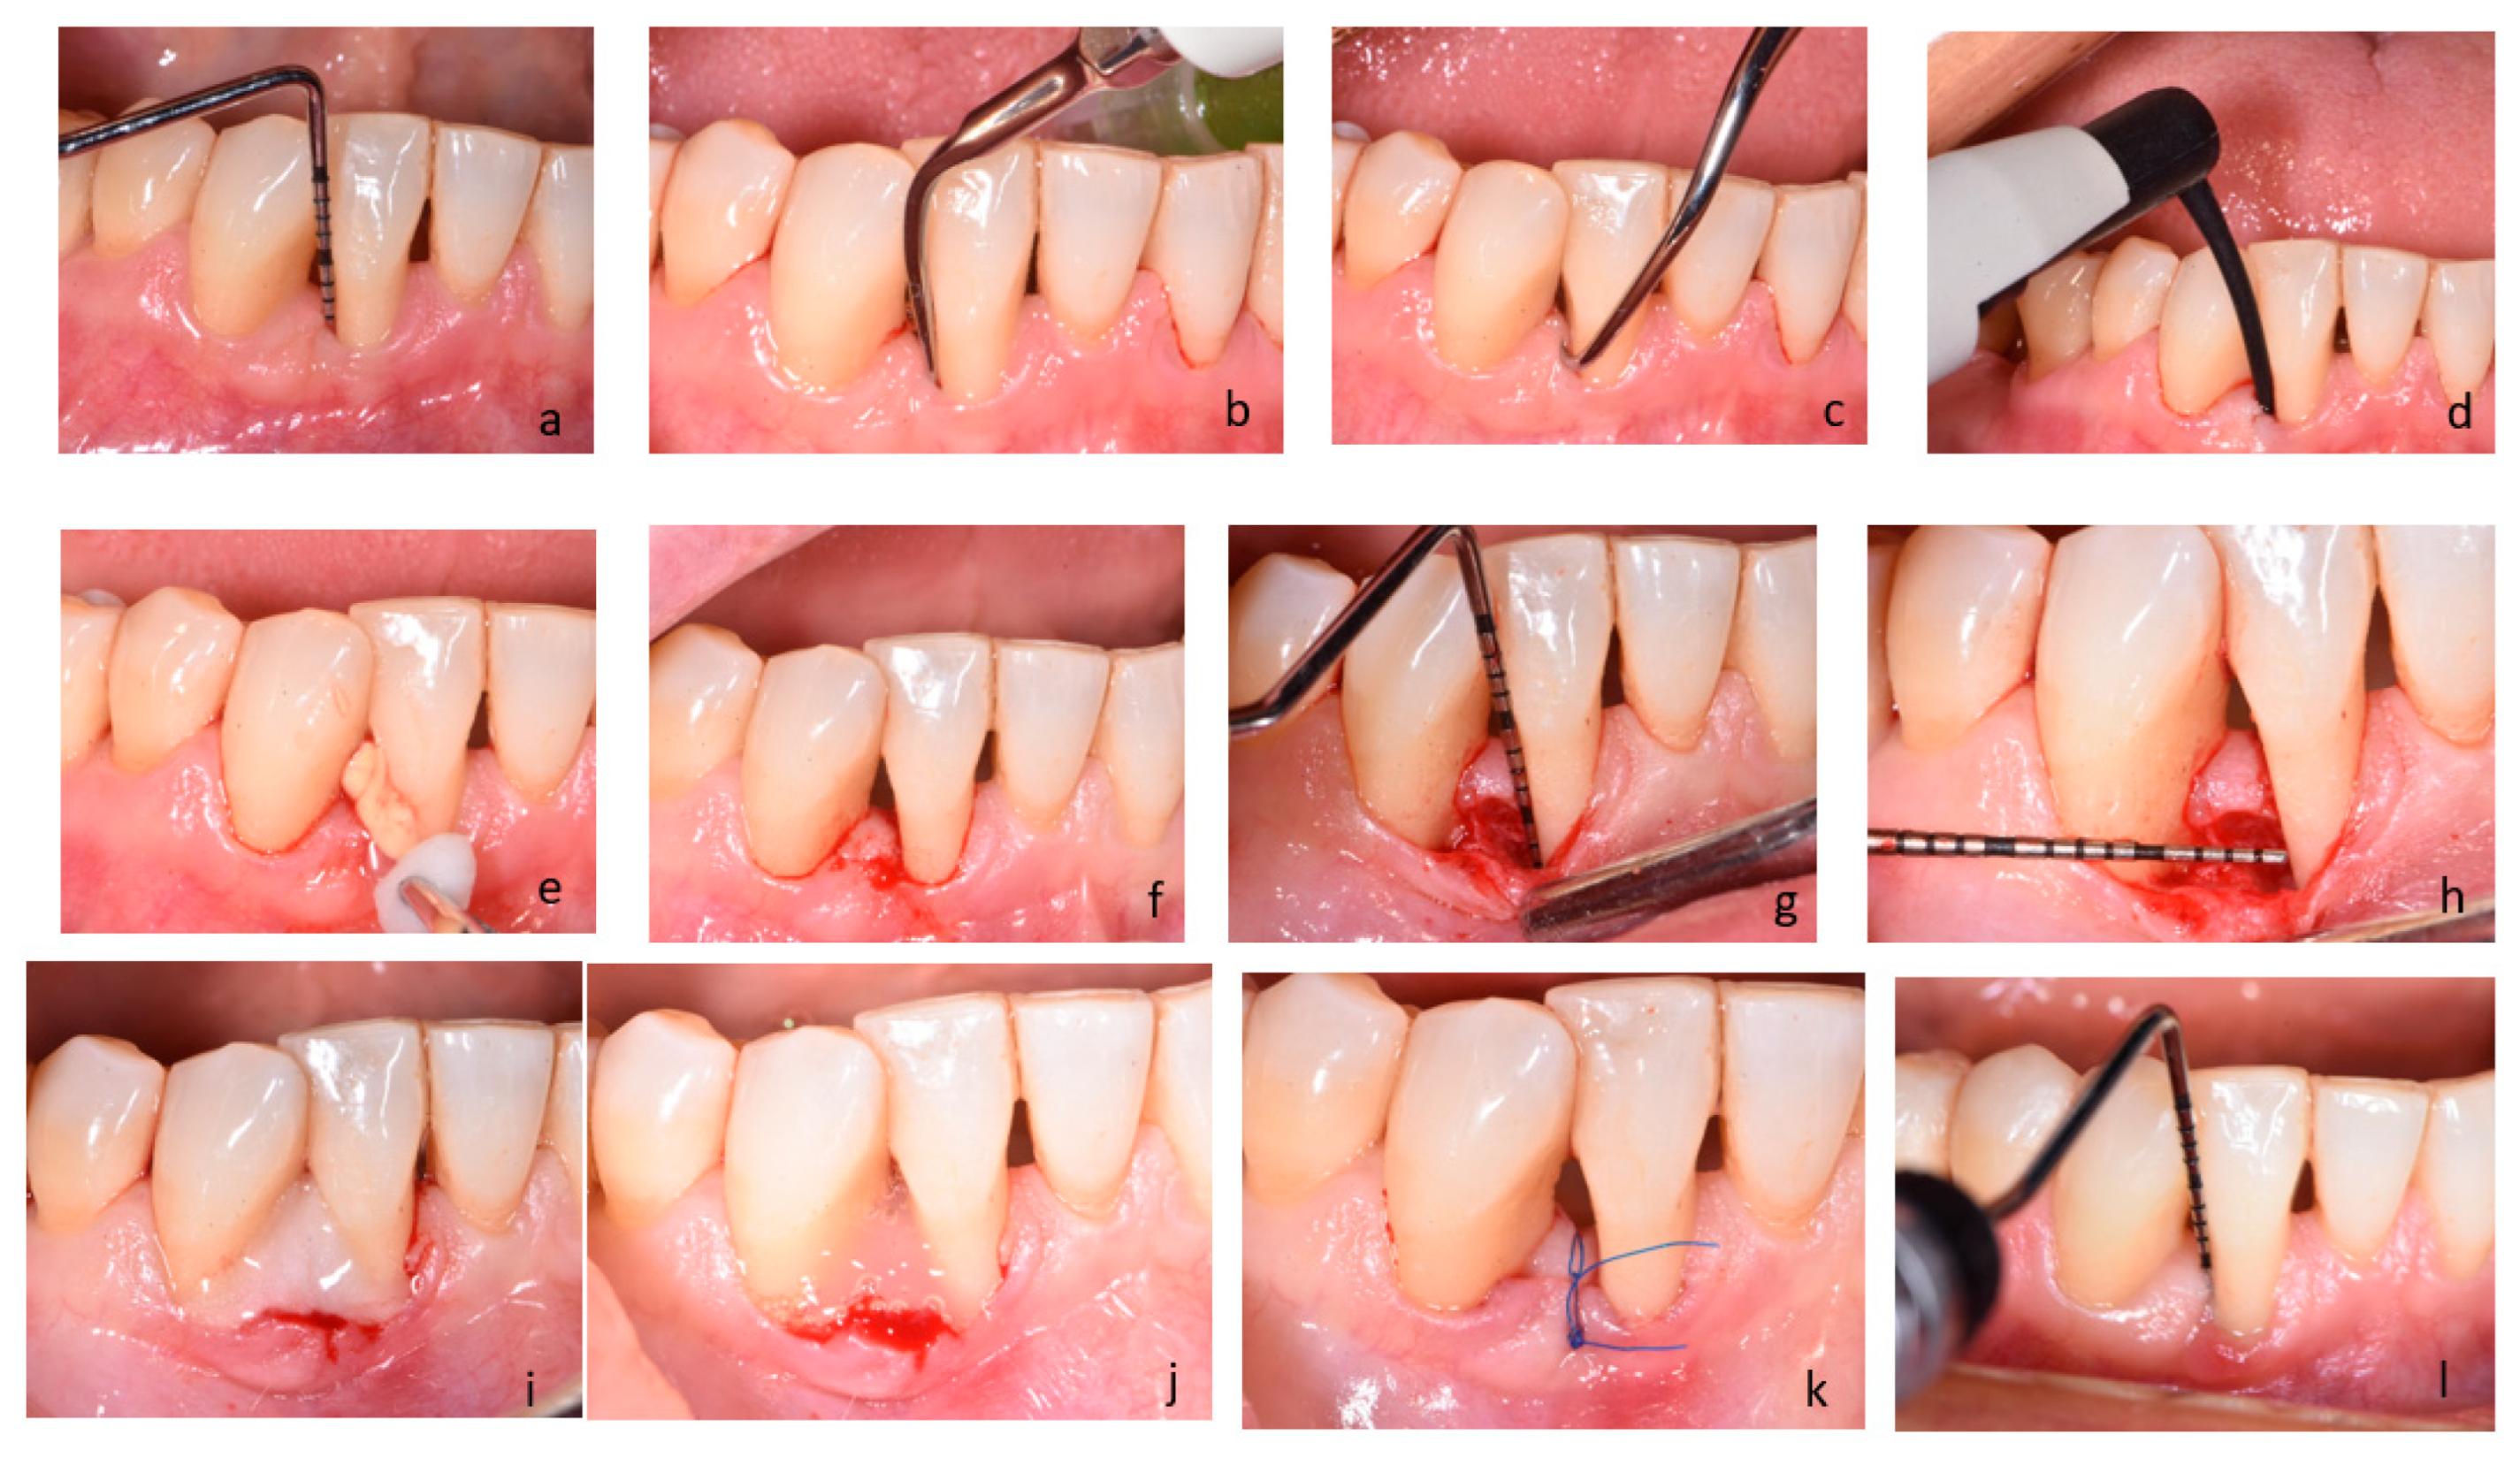

4.5. Clinical Procedure

- Cortellini, P.; Tonetti, M.S. A minimally invasive surgical technique with an enamel matrix derivative in the regenerative treatment of intra-bony defects: A novel approach to limit morbidity. J. Clin. Periodontol. 2007, 34, 87–93. [Google Scholar] [CrossRef]

- Sultan, N.; Jafri, Z.; Sawai, M.; Bhardwaj, A. Minimally invasive periodontal therapy. J. Oral Biol. Craniofac. Res. 2020, 10, 161–165. [Google Scholar] [CrossRef]

- Cortellini, P.; Tonetti, M.S. Improved wound stability with a modified minimally invasive surgical technique in the regenerative treatment of isolated interdental intrabony defects. J. Clin. Periodontol. 2009, 36, 157–163. [Google Scholar] [CrossRef]